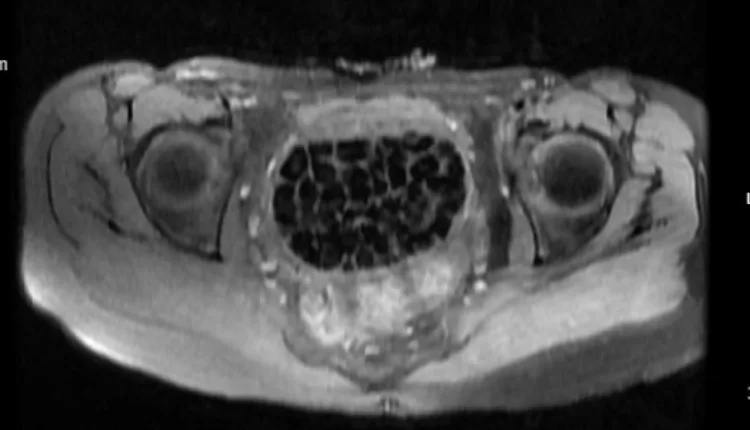

Turkish Doctors Remove 287 Stones From Young Woman

In Türkiye, 21-year-old Fatma Nur Öztürk underwent surgery after severe abdominal pain revealed a rare condition. Doctors discovered and removed 287 stones, the largest measuring 2.5 centimeters, from her bladder and vaginal area.